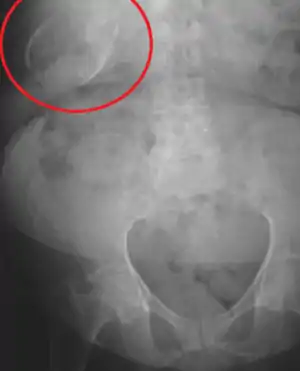

Porcelain gallbladder

Porcelain gallbladder is a calcification of the gallbladder believed to be brought on by excessive gallstones, although the exact cause is not clear. As with gallstone disease in general, this condition occurs predominantly in overweight female patients of middle age. It is a morphological variant of chronic cholecystitis. Inflammatory scarring of the wall, combined with dystrophic calcification within the wall transforms the gallbladder into a porcelain-like vessel. Removal of the gallbladder (cholecystectomy) is the recommended treatment.

| Porcelain gallbladder on X-ray | |

Abdominal radiography (X-ray), abdominal ultrasound or CT scan.